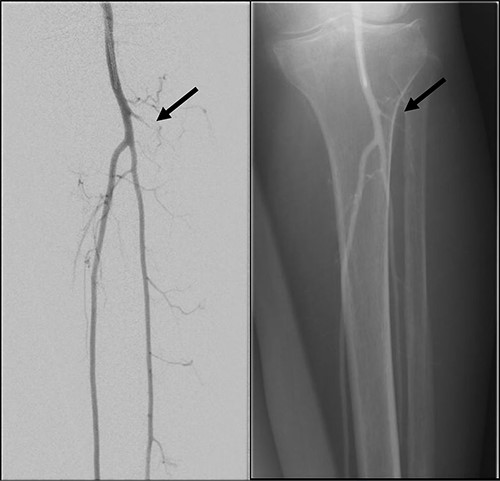

Left lower limb diagnostic angiogram showing occlusion of the ATA with poor flow (arrow).

Angiogram of left distal leg and foot showing poor flow of the distal ATA and dorsalis pedis artery (arrow).